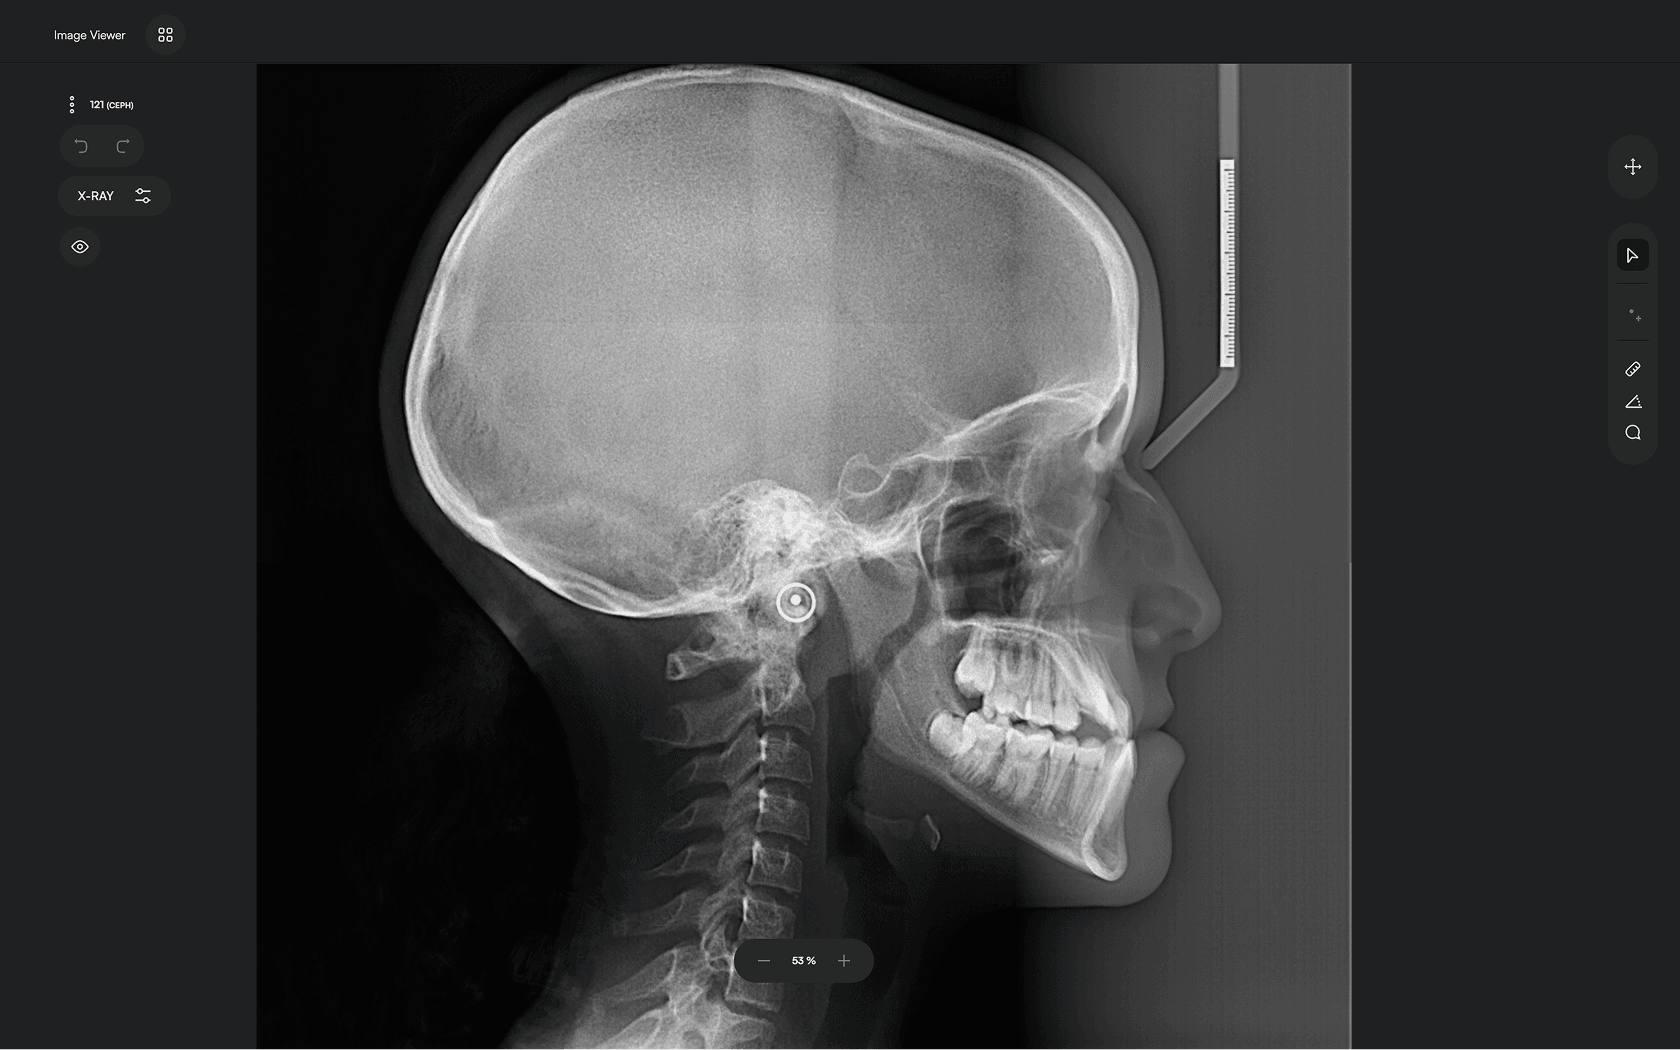

Upload X-ray

Upload your lateral cephalometric X-rays

2

Run AI

Let the software handle tracing and reporting

3